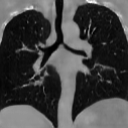

The results presented in Table 1 and 2 show our proposed method’s performance on unconditional 3D brain MR and chest CT image generation. Our proposed approach not only outperforms most comparing methods in FID and MS-SSIM metrics, it also has the lowest inference GPU memory footprint at a resolution of and was the only diffusion-based method that could be trained at a resolution of . Operating in the wavelet domain and profiting from the reduced spatial dimension also results in a relatively short inference time of / at the respective resolutions. Compared to the results presented in [23], we did not find that incorporating wavelet information into the network’s feature space (WavU-Net) increased the model’s performance. Qualitative results of our proposed method (WDM) are shown in Fig. 2 and 3. A qualitative comparison of samples produced by all evaluated methods can be found in the Supplementary Material.